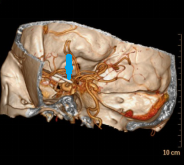

术前3D-DSA,红色剪头提示动脉瘤

图片1.png